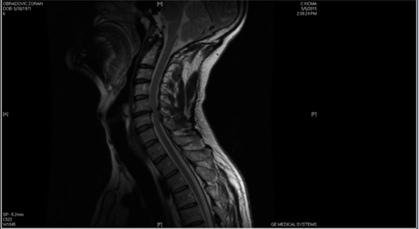

Immediately after the accident the patient noticed that he could not drive the vehicle, that is, he could not move his legs and arms. He was taken to a hospital, where a CT scan was performed. It showed the existence of a herniated disc, without visible bone trauma. The neurological findings suggested quadriparesis of medium degree, dominant/pronounced on the hands with hyperesthesia. Hyperesthesia is defined as an increased cutaneous sensitivity manifesting as stimulus-dependent neuropathic pain. While most neuropathic pain symptoms are contained within the dermatomal distribution of the affected nerve, hyperesthesia has been known to extend beyond the affected nerve’s distribution.2 In this case, the patient could not hold a bottle of water – he felt pain/sensitivity to touch. The patient was then referred to another health facility where he underwent an MR scan examination of the cervical spine region. The findings showed greater prolapse of the herniated disc and marked edema of the spinal cord in the C3/C5 vertebrae region (Figure 2). Considering the clinical findings and the MRI of the cervical spine, operative/surgical treatment was suggested. Anti-edematous therapy was also recommended and prescribed, which led to an improvement in the neurological status. After 2-3 days, the patient was able to sit in bed, and after 4-5 days he stood on his feet with a walker (orthopaedic aid). Operative treatment was postponed, and the continuation of therapy followed at the Clinic of Neurosurgery at the Clinical Centre of Serbia in Belgrade. (The accident occurred while the patient was on a vacation in Greece.)

Figure 2 MRI scan after the accident showing the edema of the spinal cord in the C3/C5 vertebrae region